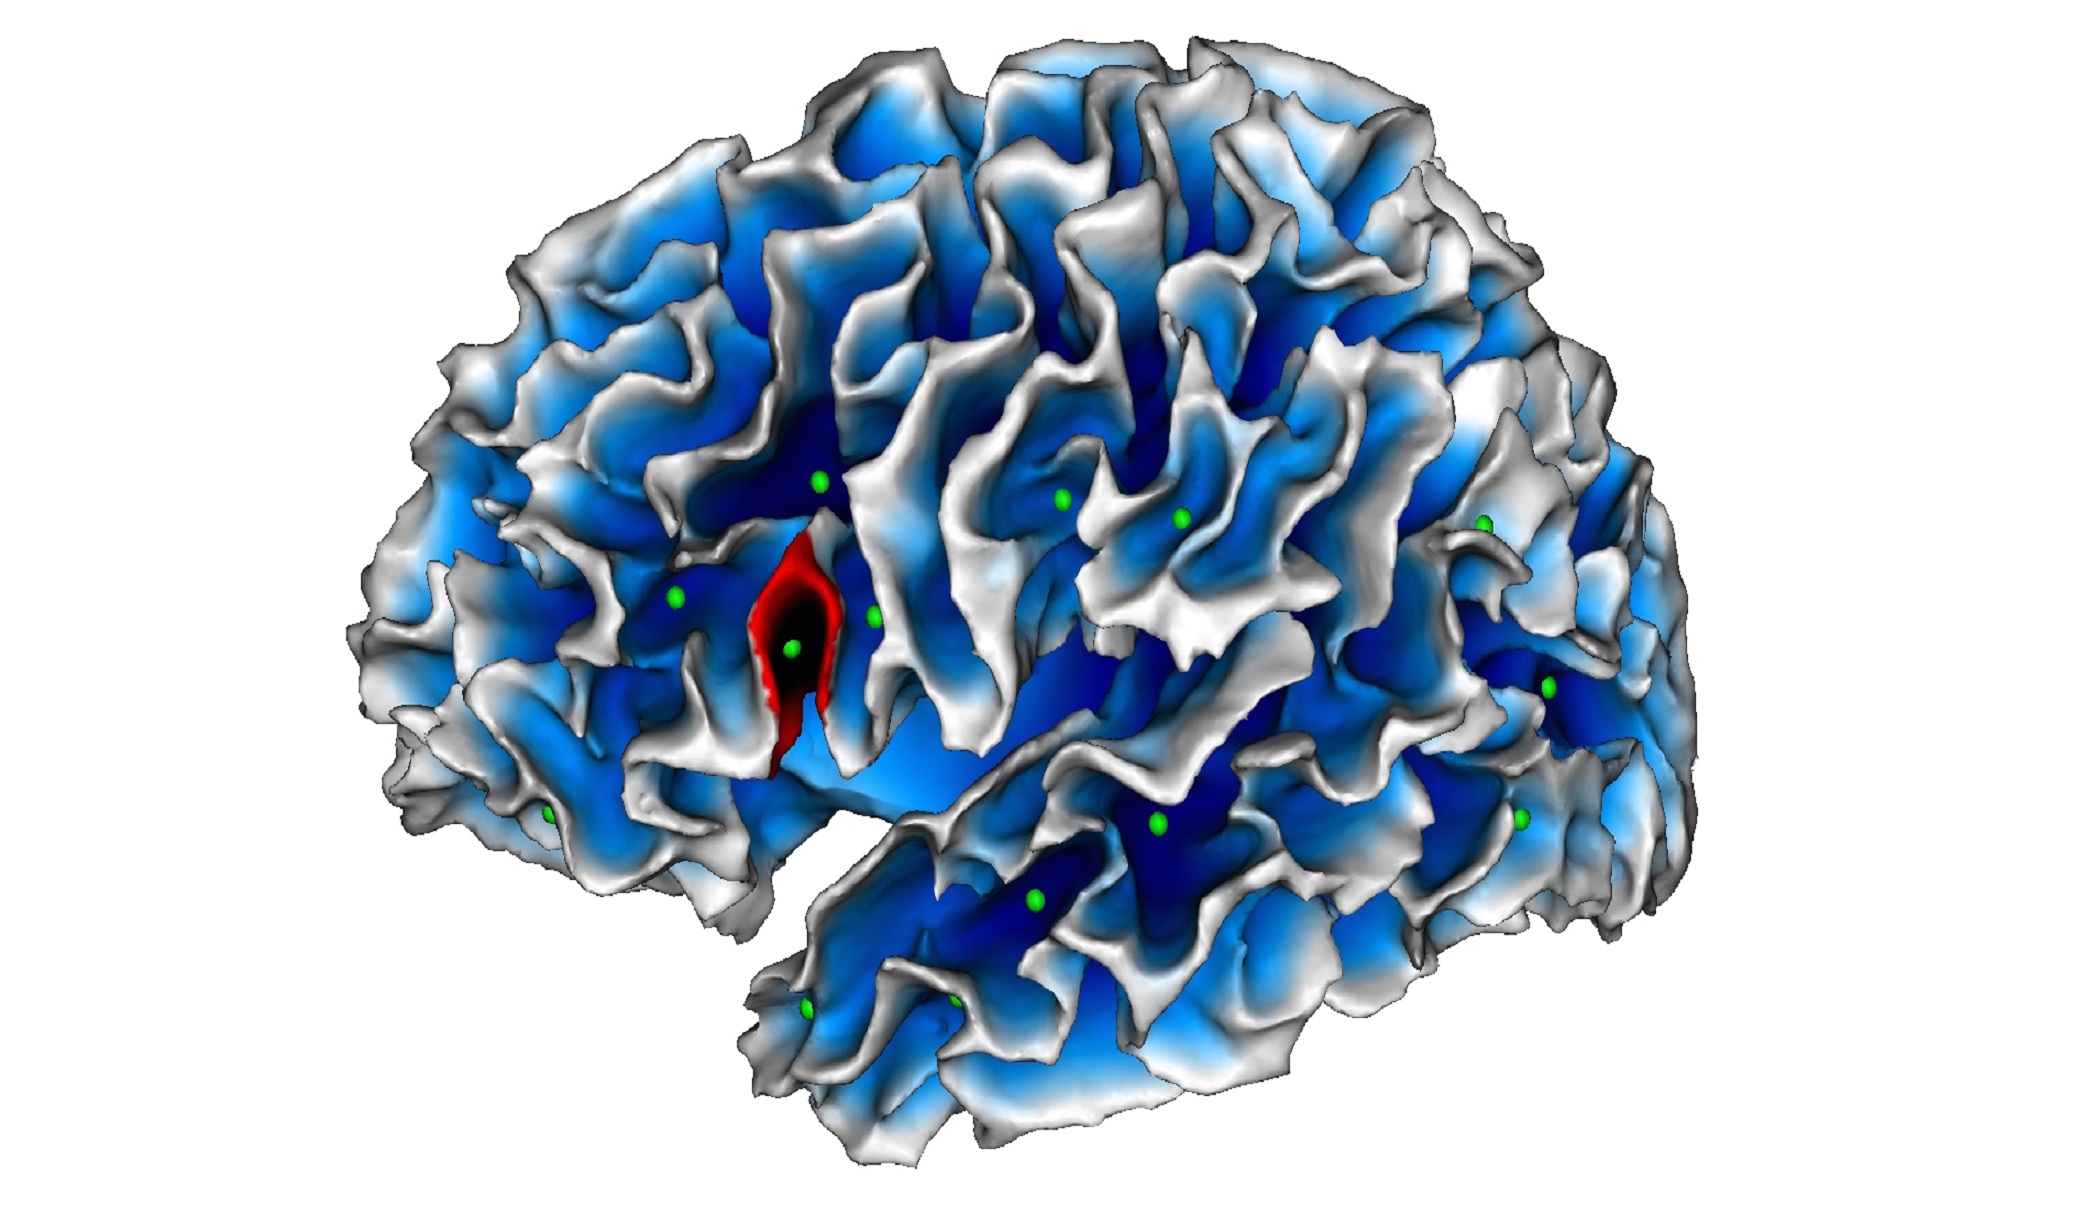

Mapa de los pliegues corticales. En verde, los hoyos surcales; en rojo, la anormalidad encontrada en niños autistas (en el área de Broca). Fuente: Scalp Team/INT/CNRS.

La anormalidad así detectada, explica el CNRS (Centro Nacional para la Investigación Científica) en una nota de prensa, consiste en un pliegue menos profundo de lo que es habitual en el área de Broca, una región del cerebro especializada en el lenguaje y la comunicación, las funciones que están deterioradas en pacientes autistas.

Los científicos del Instituto de Neurociencias de la Timone se centraron en un nuevo marcador geométrico llamado "hoyo surcal". Este es el punto más profundo de cada surco de la corteza cerebral, a partir del cual se desarrollan todos los puntos de los pliegues de la superficie del cerebro. Por lo tanto, existen desde una fase de desarrollo muy temprana, probablemente bajo influencias genéticas, lo que significa que son indicadores que permiten comparar diferentes individuos.

Los científicos del Instituto de Neurociencias de la Timone se centraron en un nuevo marcador geométrico llamado "hoyo surcal". Este es el punto más profundo de cada surco de la corteza cerebral, a partir del cual se desarrollan todos los puntos de los pliegues de la superficie del cerebro. Por lo tanto, existen desde una fase de desarrollo muy temprana, probablemente bajo influencias genéticas, lo que significa que son indicadores que permiten comparar diferentes individuos.

Basándose en los hallazgos de la resonancia magnética, los científicos observaron los hoyos surcales de 102 niños de entre 2 y 10 años, que fueron colocados en tres grupos (con trastorno autista, con trastorno generalizado del desarrollo no especificado, y niños con desarrollo normal).

Mediante la comparación de estos tres grupos, descubrieron que en el área de Broca, la profundidad máxima de un surco era inferior en los niños autistas en comparación con los otros dos grupos. Curiosamente, esta atrofia muy localizada se correlacionó con el rendimiento en comunicación social de los niños del grupo autista: cuanto más profundos eran los hoyos surcales, más deterioradas estaban sus habilidades con el lenguaje.

Basándose en los hallazgos de la resonancia magnética, los científicos observaron los hoyos surcales de 102 niños de entre 2 y 10 años, que fueron colocados en tres grupos (con trastorno autista, con trastorno generalizado del desarrollo no especificado, y niños con desarrollo normal).

Mediante la comparación de estos tres grupos, descubrieron que en el área de Broca, la profundidad máxima de un surco era inferior en los niños autistas en comparación con los otros dos grupos. Curiosamente, esta atrofia muy localizada se correlacionó con el rendimiento en comunicación social de los niños del grupo autista: cuanto más profundos eran los hoyos surcales, más deterioradas estaban sus habilidades con el lenguaje.